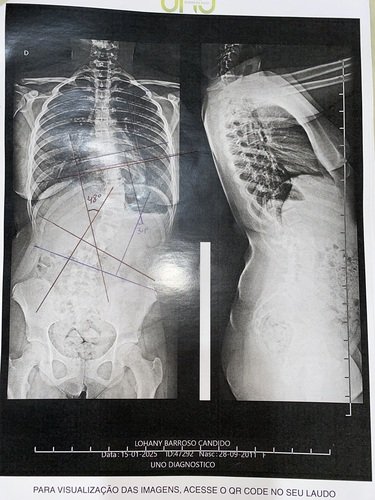

Cirurgia de coluna da Lohany

Me chamo Lorena,sou mãe da Lohany de 13 anos,que está com escoliose severa 48 graus ela está há 3 meses na fila de espera do SUS e sem previsão para data da cirurgia devido a fila de espera ser muito grande. sente muito dor não consegue pas ver tudo

Me chamo Lorena,sou mãe da Lohany de 13 anos,que está com escoliose severa 48 graus ela está há 3 meses na fila de espera do SUS e sem previsão para data da cirurgia devido a fila de espera ser muito grande. sente muito dor não consegue passar muito tempo em pé,pois os pés incham os remédios que ela toma já não estão fazendo efeito,devido ao problema na coluna não consegue realizar atividades escolares,peço encarecidamente que nos ajude para que ela possa voltar a ter qualidade de vida,desde já agradeço e que Deus vos abençoe